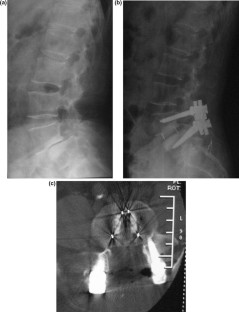

Fig. 2